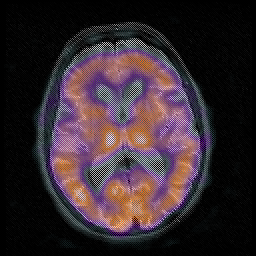

Huntington's Chorea, MR -- Slice #10

[Home][Help][Clinical] Slice 10